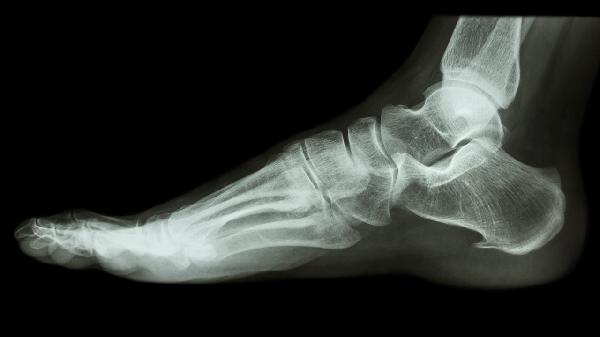

骨折后45天是否达到临床愈合标准与损伤程度、年龄、营养状况等因素相关。单纯线性骨折且接受规范固定者,此时骨痂已初步形成,在医生指导下可尝试部分负重行走,初期建议使用拐杖分担压力,选择硬底鞋提供支撑,避免跑跳或长时间站立。康复期间应定期复查X线,观察骨痂生长是否连续、对位是否良好。

开放性骨折、粉碎性骨折或伴有血管神经损伤者,愈合周期往往延长至8-12周。若过早拆除外固定或过度负重,可能造成骨折线移位甚至内固定物断裂。糖尿病患者、骨质疏松患者及吸烟人群更需谨慎,这类人群骨再生能力较弱,二次骨折风险显著增加。如行走时出现局部刺痛、肿胀加剧或异常活动感,应立即停止负重并就医。